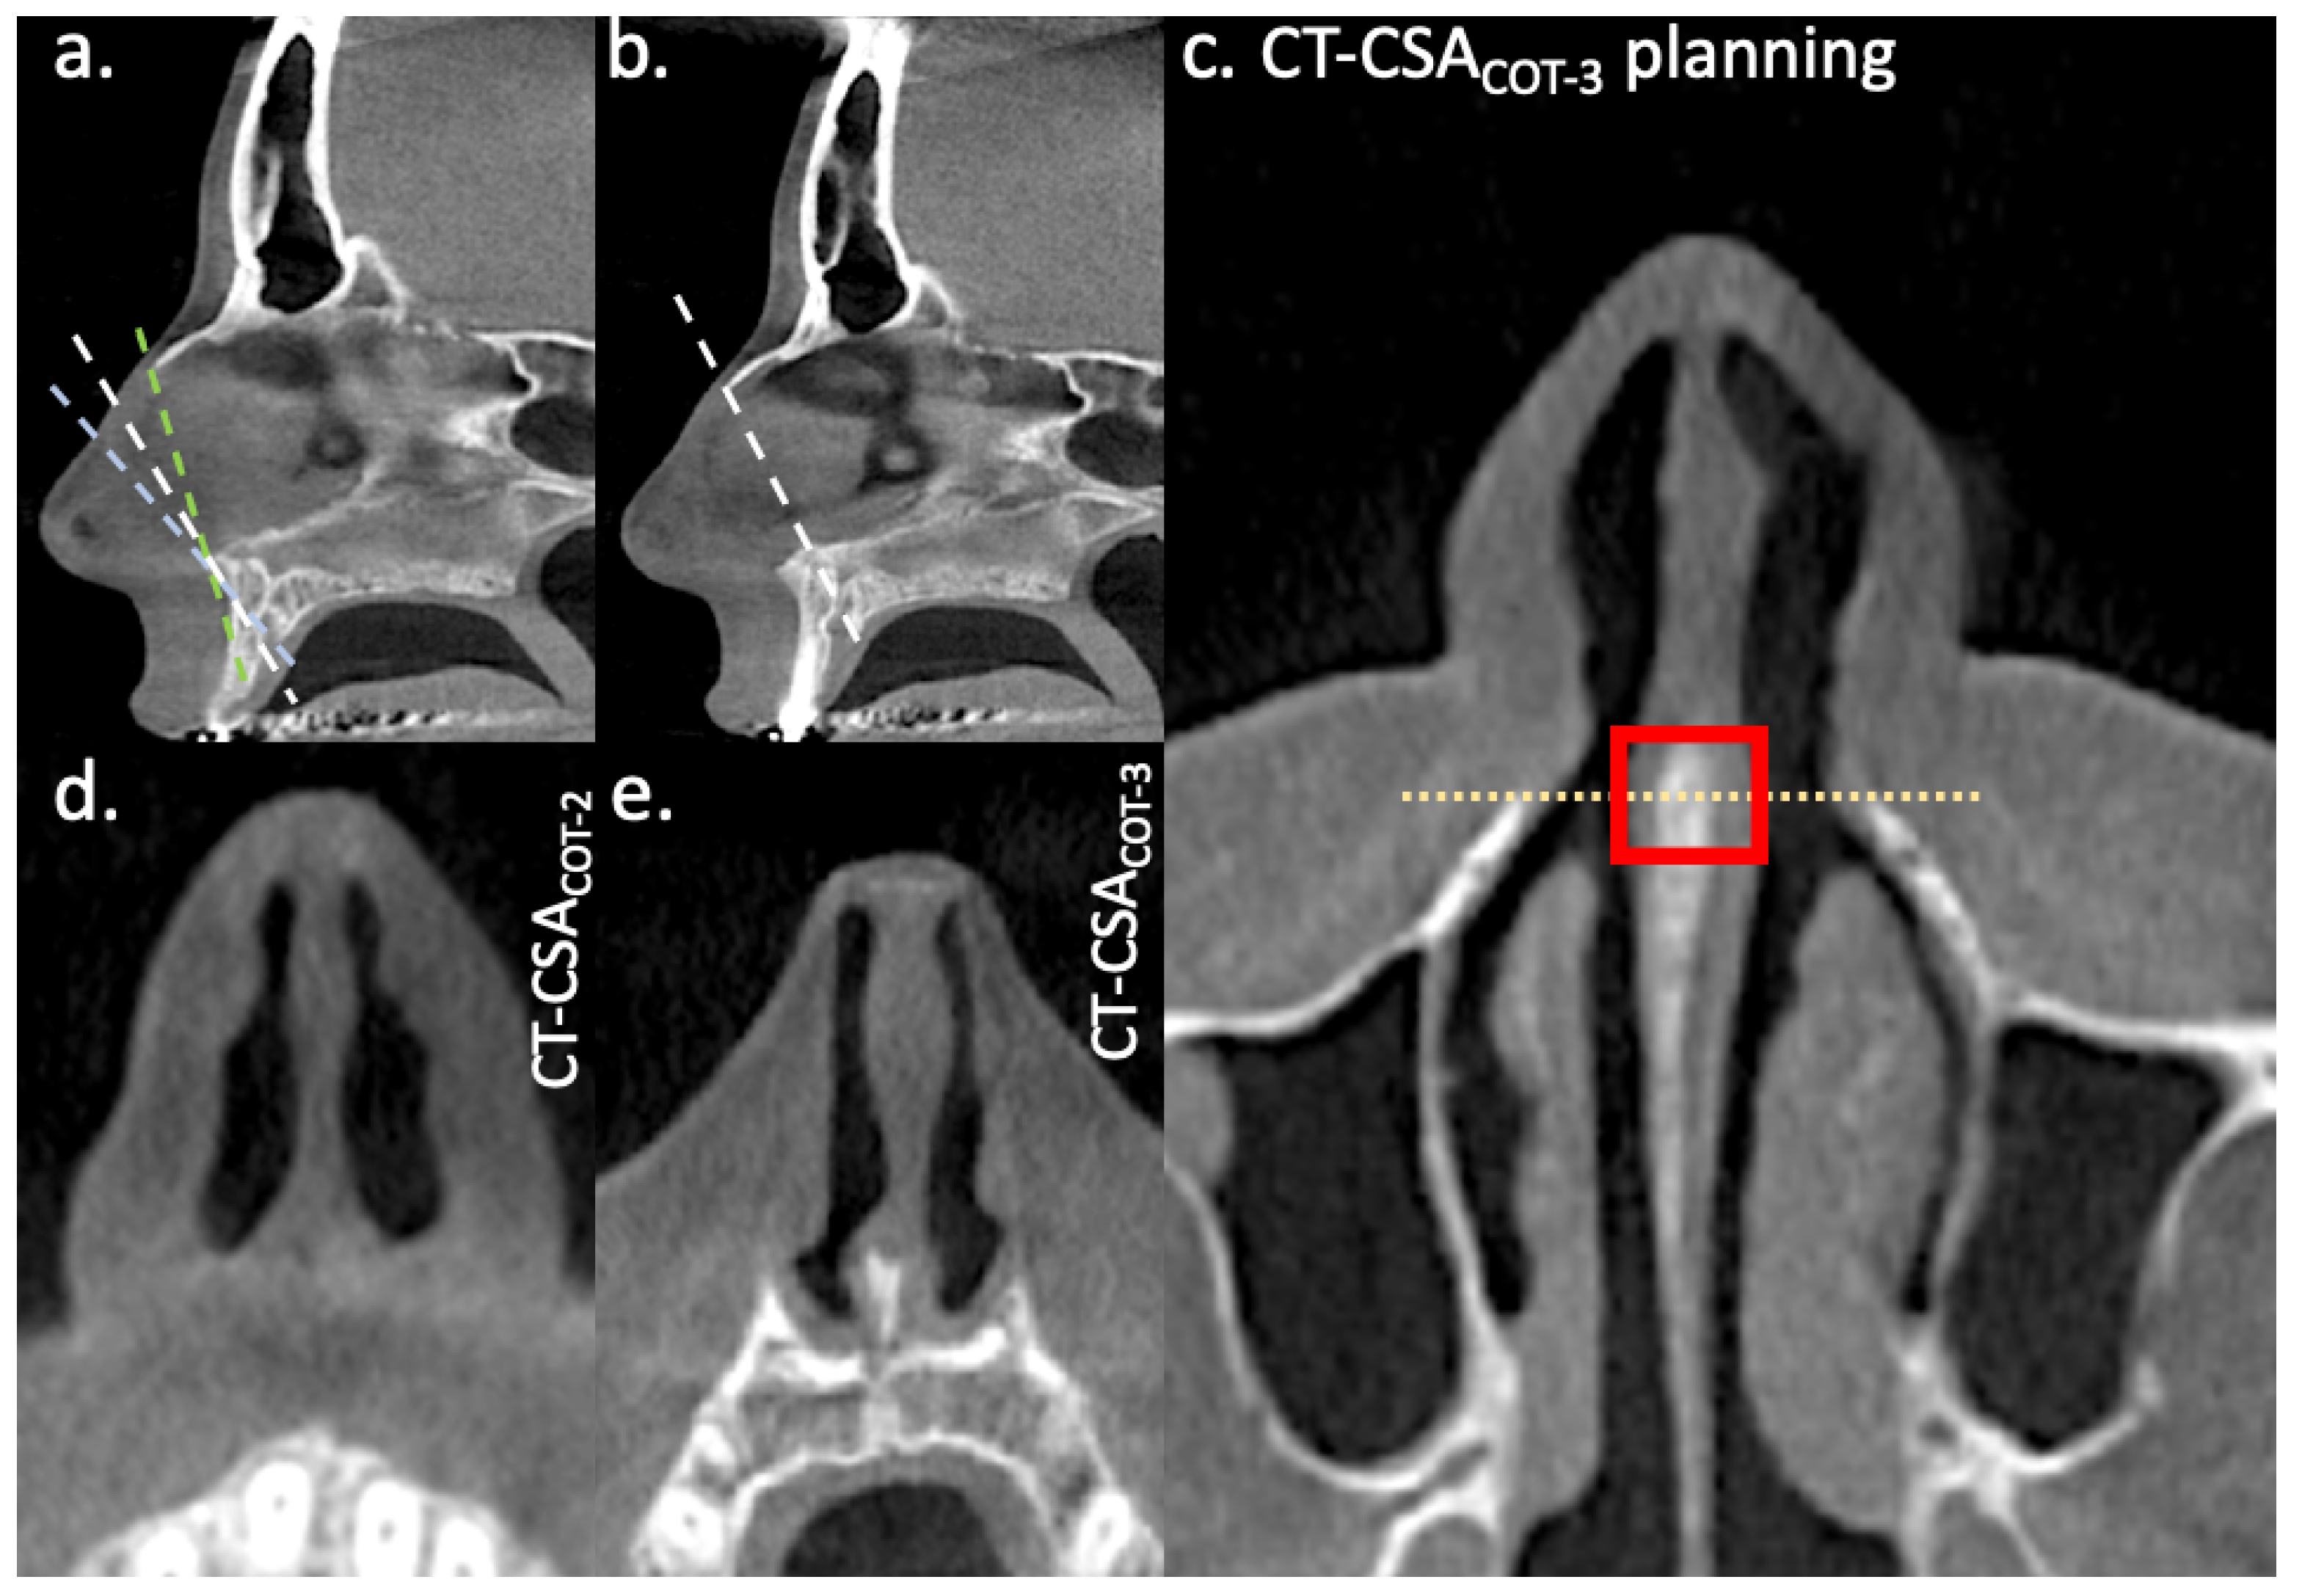

2.2. CT-Planes